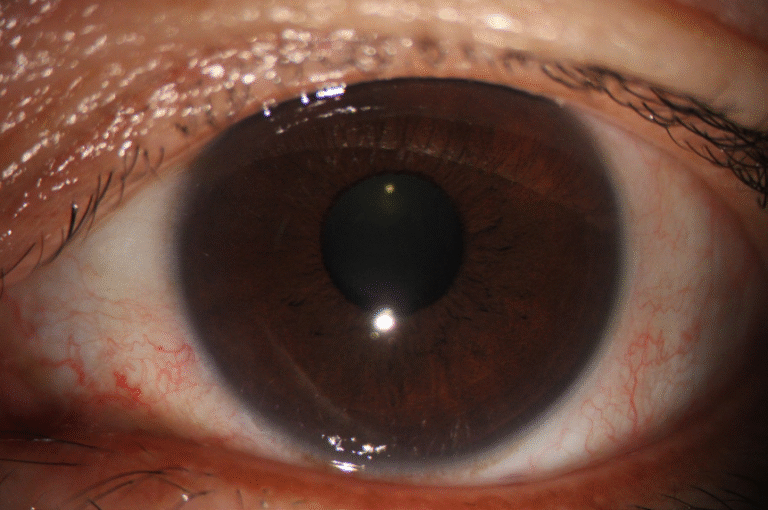

Dry Eye

Full ocular surface analysis

Advanced Dry Eye analysis

Built-in Digital Analysis